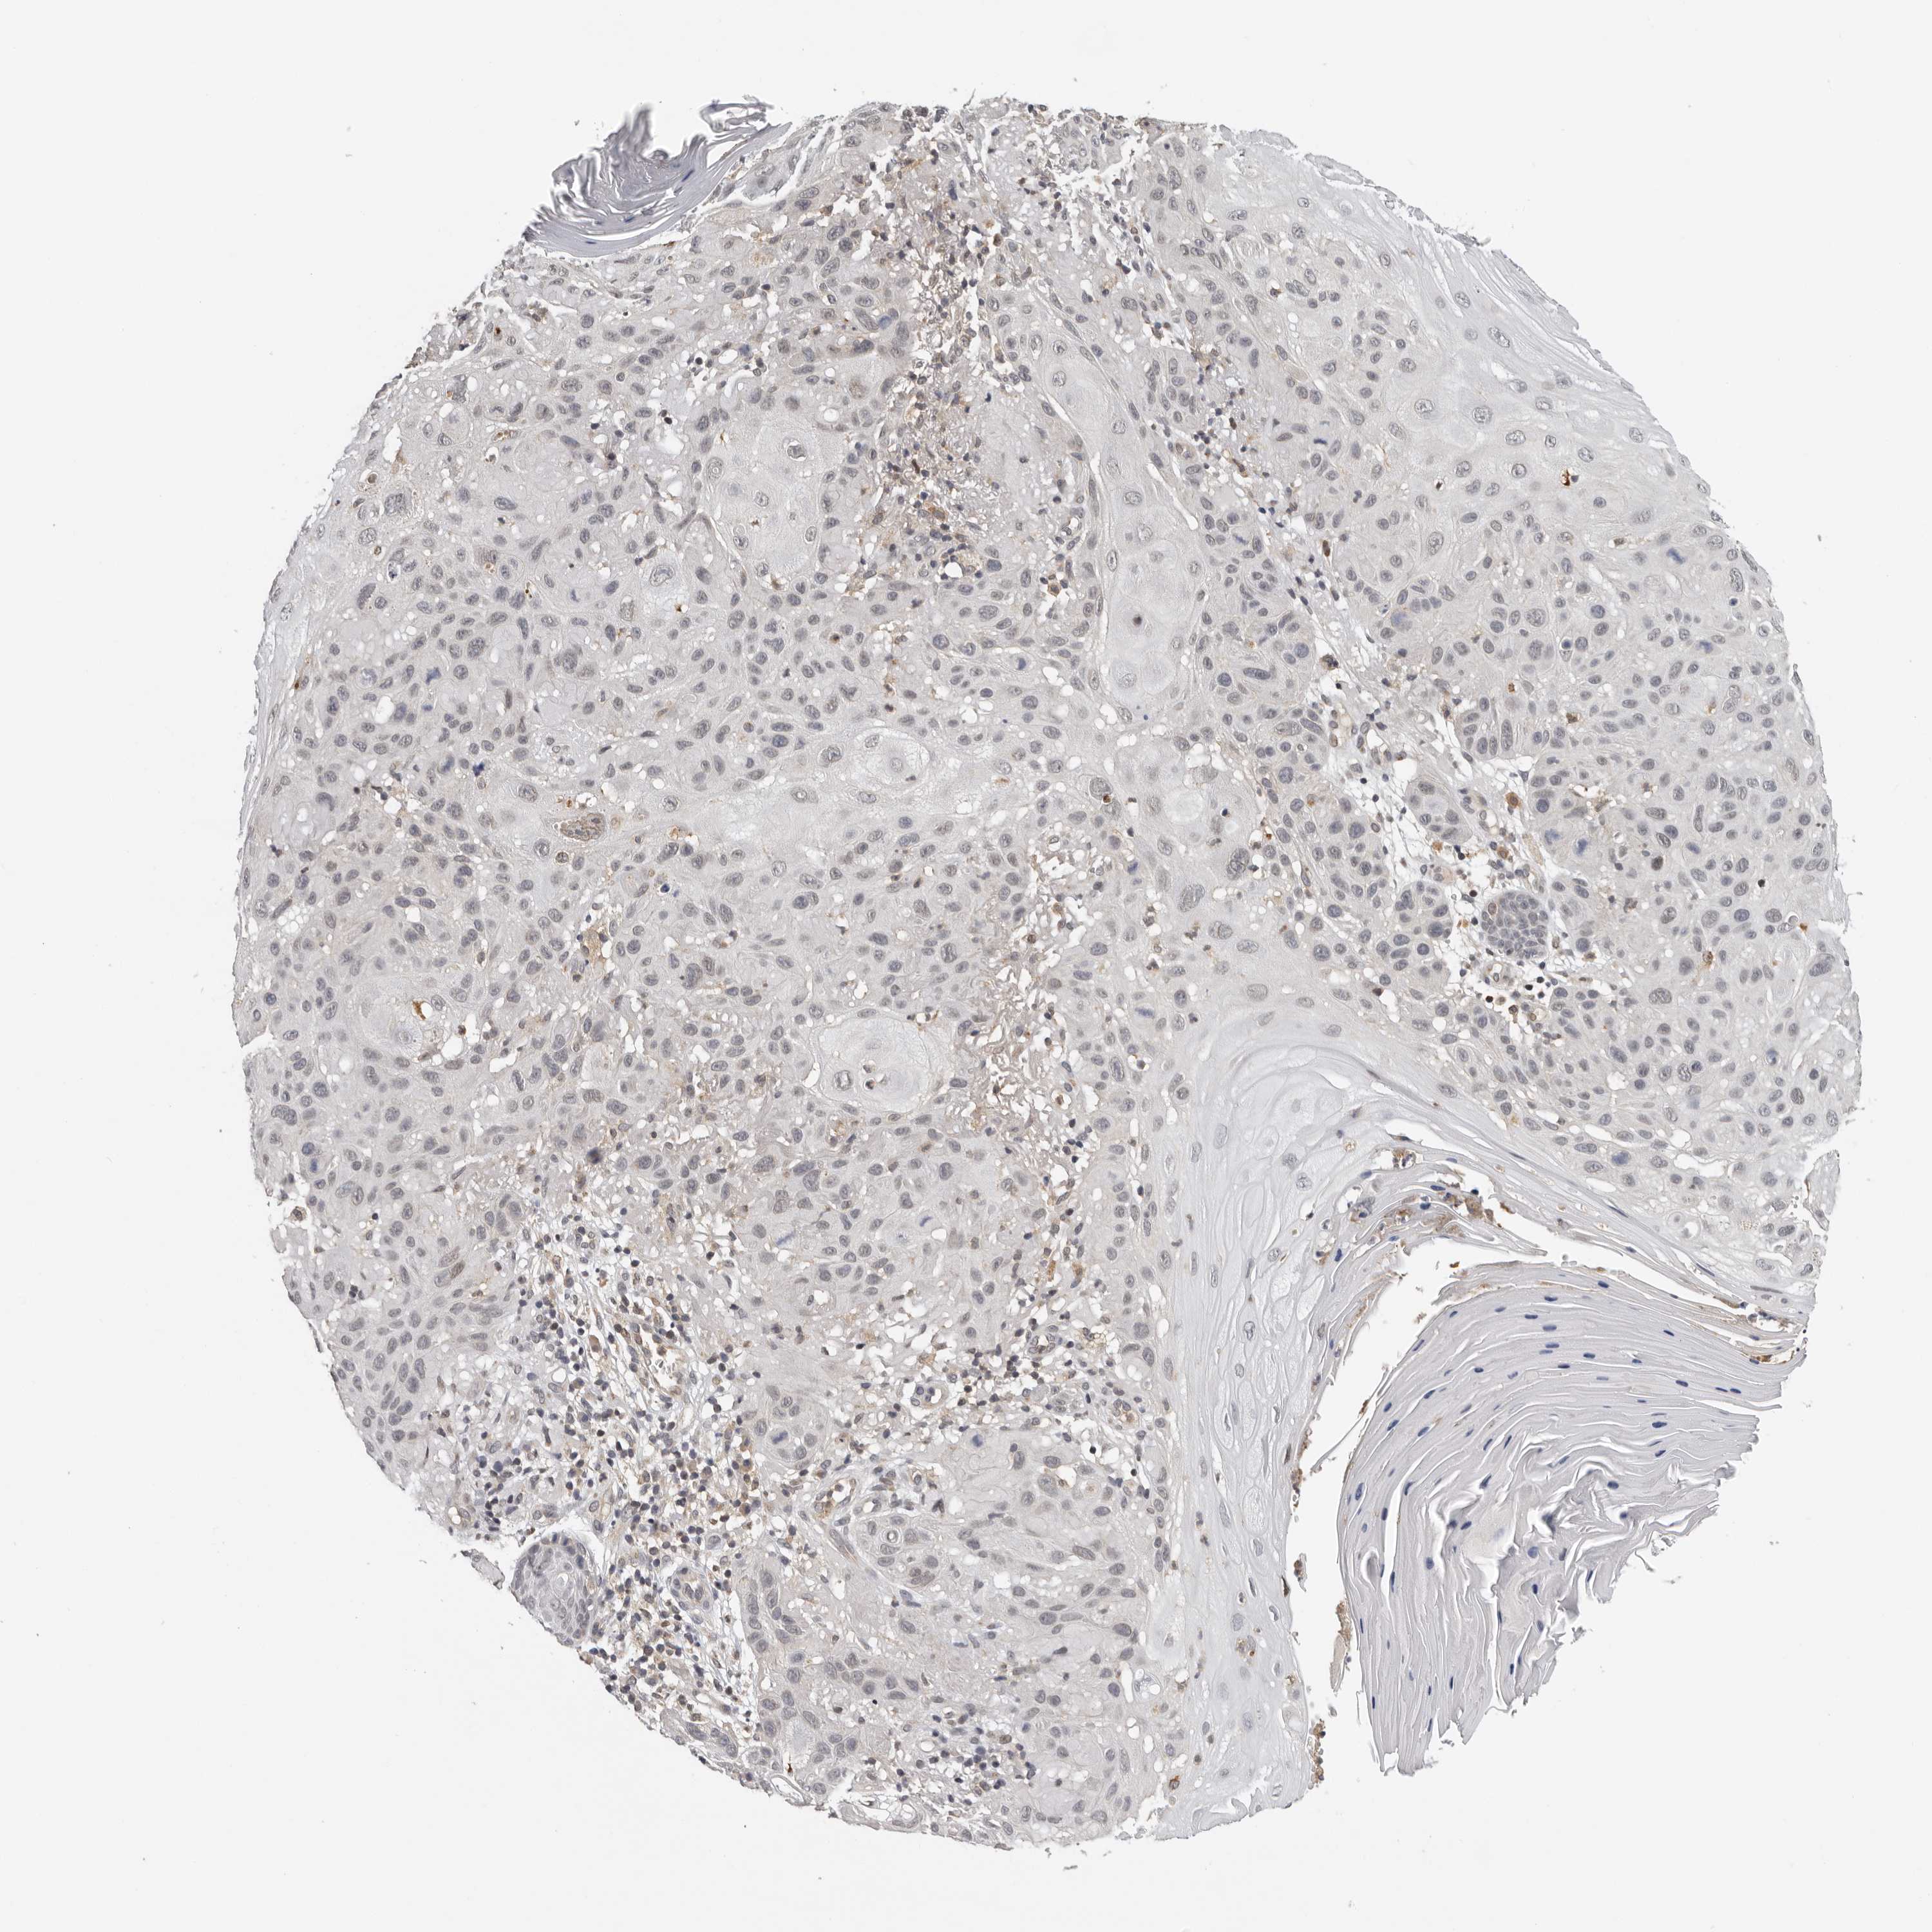

Basal cell and squamous cell cancer

SKIN CANCER - Protein expressioni

A mouse-over function shows sample information and annotation data. Click on an image to view it in a full screen mode. Samples can be filtered based on level of antibody staining by selecting one or several of the following categories: high, medium, low and not detected. The assay and annotation is described here.

Each image is clickable and will lead to virtual microscopy that enables deeper exploration of all samples and also displays staining intensity scores, fraction scores and subcellular localization as well as patient and tissue information for each sample.

Antibody HPA024795

Squamous cell carcinoma, metastatic, NOS